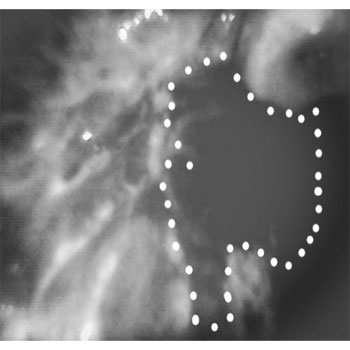

Clinical Image and Blue light image with High intensity of light, Both Images are filtered for better appreciation

The HD camera with 5MP will enables visualizations more clearly

Image of the lesion after filtering with smaller head and camera in the device after filtering.